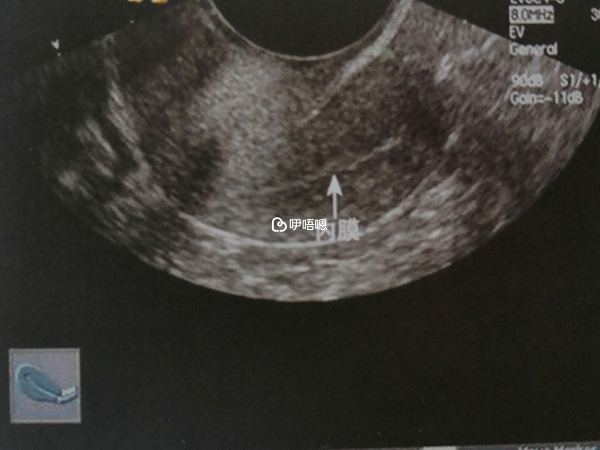

六號不相信去醫院b超內膜11mm。有史以來從來沒有這麼厚過的。但是沒有看見妊娠囊。醫生說月經不調我的排卵時間可能會晚也不一定。七號驗了血值那個hgg是1584,孕酮18.94,醫生說孕酮最好有25。